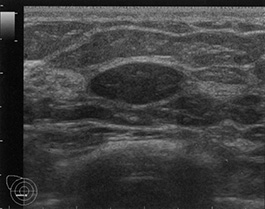

マンモグラムでは、散在する線維腺乳房組織を特定できます。これにより、その人の乳房組織の種類が特定され、乳房にしこりがあれば明らかになります。

- 超音波:このオプションでは、高周波音波を使用して乳房組織の画像を作成します。ハンドヘルド デバイスまたは自動スキャナーを使用すると、乳房全体の 3D 画像を作成できます。